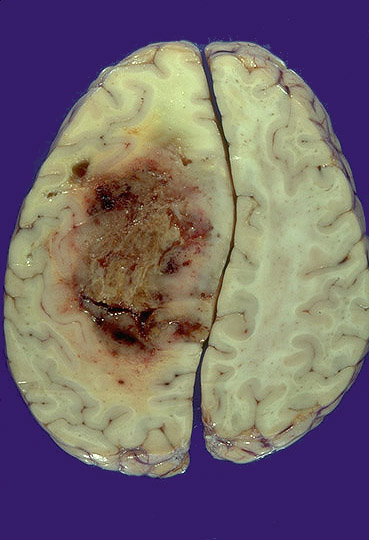

Enfermedades Tumorales

La figura de la izquierda muestra un tumor infiltrante del hemisferio cerebral derecho consistente con un glioblastoma multiforme.